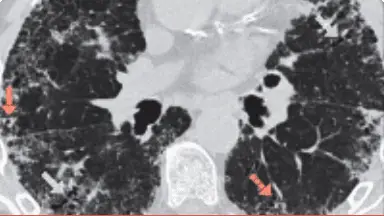

Imagistica HRCT în fibroza pulmonară

Tomografia computerizată de înaltă rezoluție este esențială pentru diagnosticarea precisă a PID.13